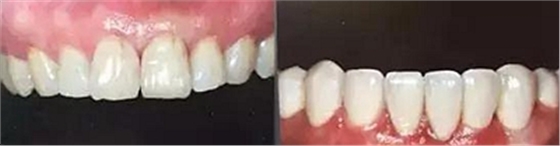

上下前牙正面影像

構圖包含4-6顆前牙,中切牙為對焦中心

采用黑背景

拍攝比例:1:1.8,光圈f38,快門速度1/125,閃光強度M/4

口腔攝影方法與技巧

上下前牙側(cè)面影像

頭部向非拍攝側(cè)轉(zhuǎn)45°角

使側(cè)切牙、尖牙及雙尖牙暴露在照片中心

拍攝比例:1:1.8,光圈f38-45,快門速度1/125-180,閃光強度M/4